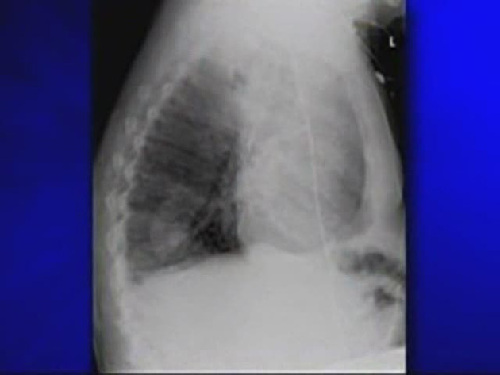

榮恩·斯維頓因肺中長(zhǎng)出豌豆苗肺功能衰竭

????美國(guó)麻薩諸塞州男子榮恩·斯維頓最近一段時(shí)間總是咳嗽不止,身體日益衰弱。然而,為他治療的醫(yī)生卻一直找不到病因,他既沒有患上肺癌,也沒有長(zhǎng)腫瘤。最終醫(yī)生從他肺部的X光透視片上發(fā)現(xiàn),居然有一棵豌豆苗在他的肺里生長(zhǎng)。這粒豌豆在斯維頓的肺中發(fā)芽生根,長(zhǎng)成了一棵近4厘米長(zhǎng)的植物,導(dǎo)致他的肺功能衰竭。

X光片顯示出斯維頓肺中的豌豆苗